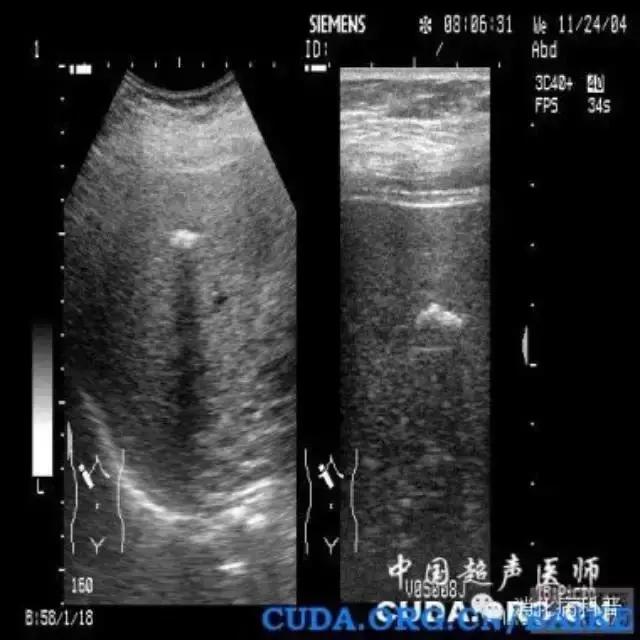

肝内钙化灶在B超上会出现类似结石一样的强回声,或CT检查时表现为肝内高密度影像。因此有时肝内钙化灶与肝内胆管结石容易相互混淆。所以很多人所谓的“肝内胆管结石”很可能只是肝内钙化灶。虽然肝内钙化灶和肝内胆管结石都有相似的强回声团及声影,但钙化灶一般不引起肝胆管扩张。

肝内胆管结石常见症状是肝区轻微疼痛,重者可引起剧痛,高热、黄疸等,并在胆管远端出现扩张。在超声检查时,肝内胆管且结石的“强回声光团”大都沿肝内胆管走向分布,这与钙化灶是完全不同的。所以B超发现肝内有“光团”后,要区别是肝内钙化灶还是肝内胆管结石,一个重要依据就是看远端胆管有没有扩张,而扩张的胆管内最容易形成淤滞性泥沙样结石。如果强光团周围出现液性暗区,同时伴有近侧胆管狭窄和远侧胆管扩张,更能肯定为肝内胆管结石。

肝内钙化灶的B超图像特点是:呈“品字”或“等号”状分散的强回声,走行于胆管腔外,后方大多无声影或淡的声影,同时无肝内胆管扩张。